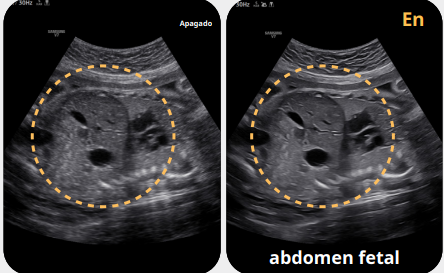

Mejore su apreciación sobre la evaluación del problema basado en un rendimiento de imagen excepcional impulsado por el motor de imagen principal de Samsung, Crystal Architecture™. El motor de imagen premium combina las ventajas del procesamiento de imágenes 2D mejorado y la expresión detallada del procesamiento de la señal de color. El V7 proporcionará una calidad de imagen sobresaliente para un diagnóstico de confianza.